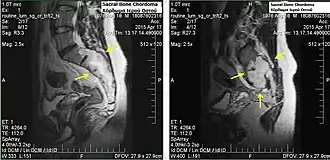

Chordomas can arise from bone in the skull base and anywhere along the spine. The two most common locations are cranially at the clivus and in the sacrum at the bottom of the spine.[2] Very rarely, chordomas present outside of the skull base or spine; these are called extra axial chordomas.[3]

Sacral chordomas make up 2 to 4% of all primary bone tumours and 44% of all primary sacral tumours, thus making it the most common malignant sacral tumor. About 50 to 60% of chordomas are located in the sacrococcygeal region. Males aged between 40 and 50 years are twice as likely as women to get sacral chordoma.[28]